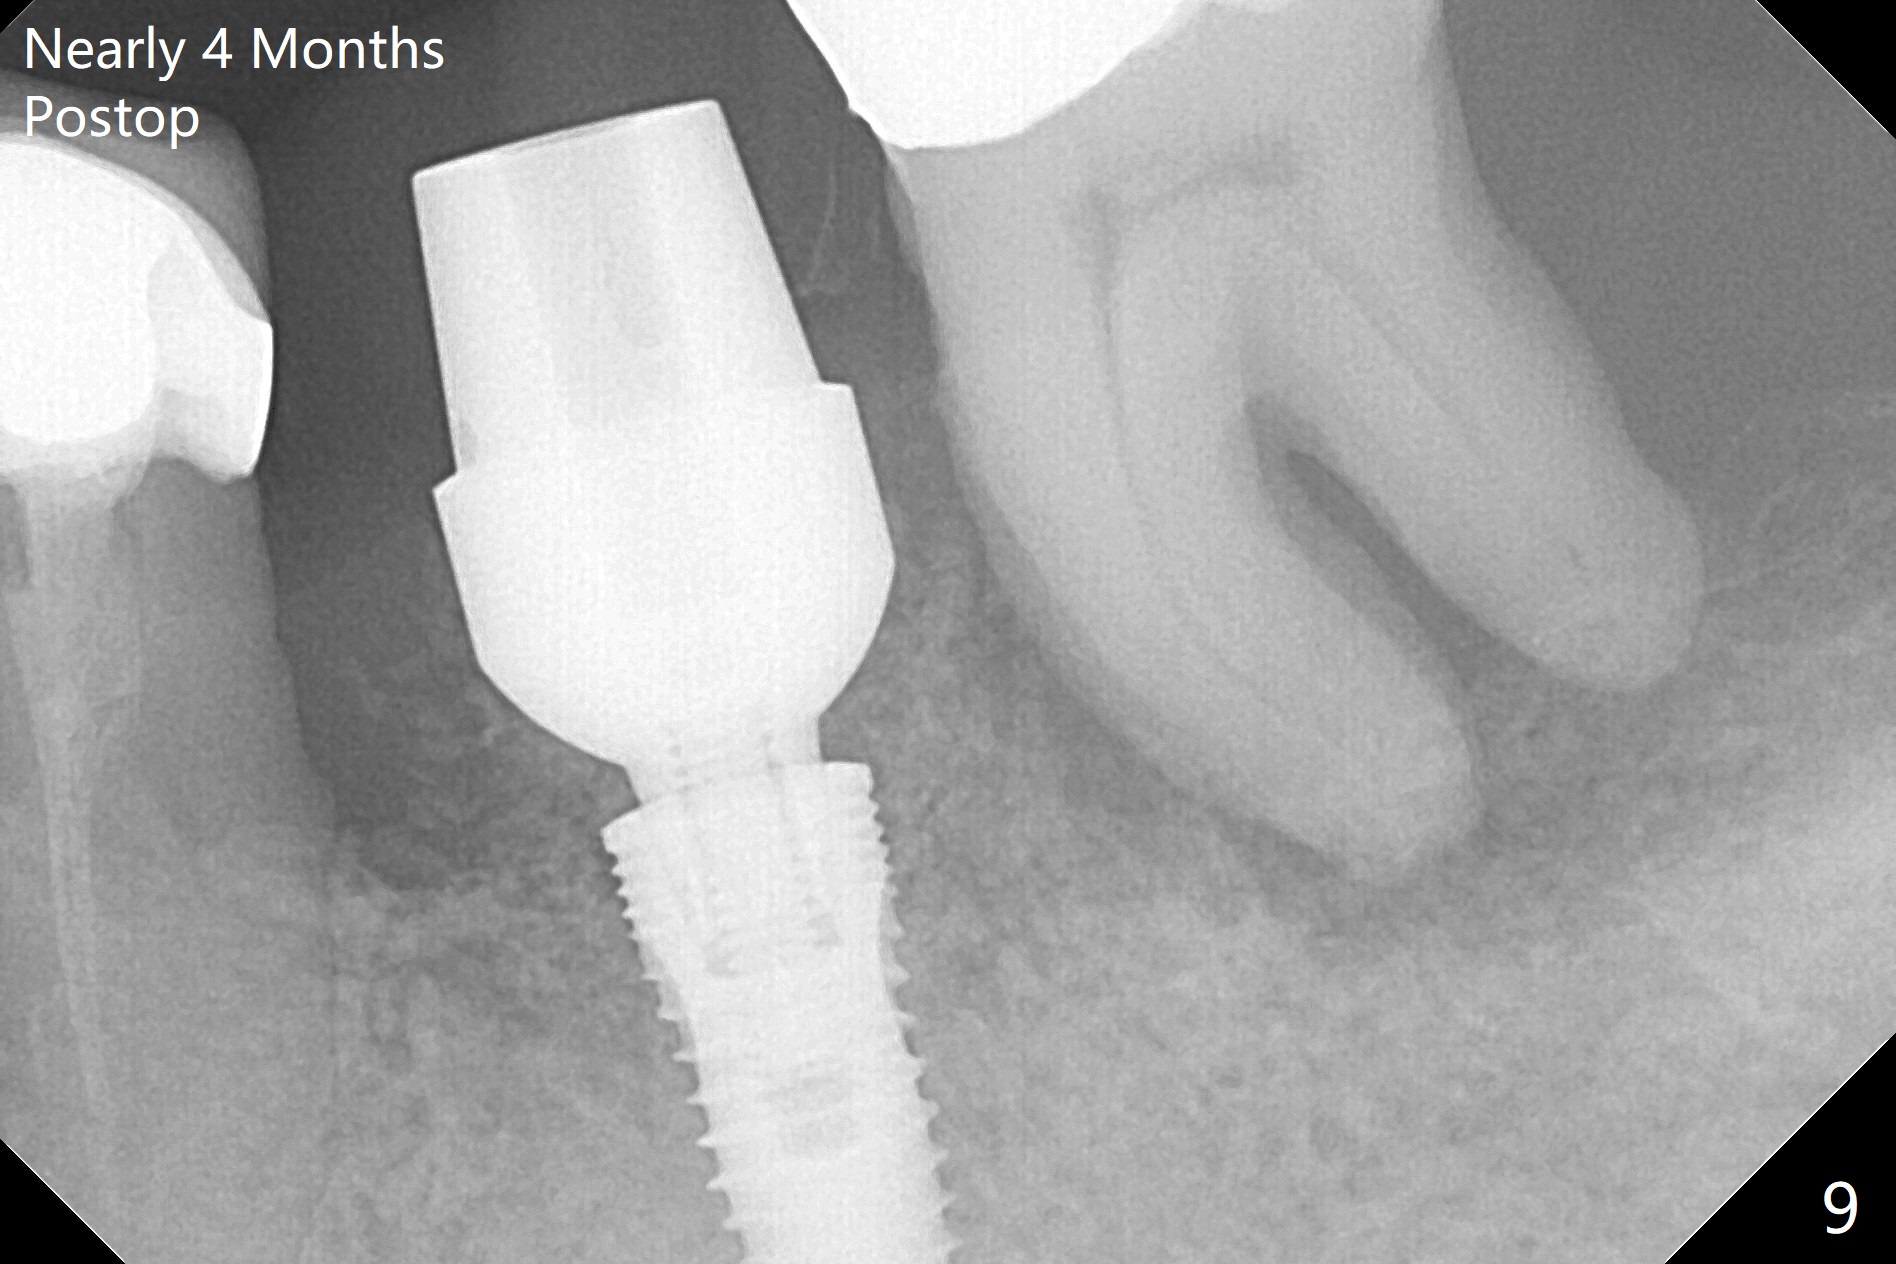

After extraction of the supraerupted tooth #19 with severe buccal gingival recession, the buccal and lingual plate are found to be lost. The sockets are fused and flat without the septum. The bone is hard and painful for the initial osteotomy with infiltration anesthesia (Fig.2). Following block anesthesia, the initial osteotomy depth extends to 8 mm (Fig.3,4). With apparent 4.9 mm clearance, the osteotomy is further extended to 10 mm. The osteotomy walls are apparently intact without severe hemorrhage after each drill. Due to the thick gingiva and severe bone loss, a 5x12 mm implant is intentionally placed 3 mm above the base of the socket bone (Fig.5,6 (yellow dashed line)). Vanilla Cortical and Cancellous allograft (Fig.6 *) is placed around the exposed implant and 7.8x5(6) mm abutment with 4 and 2 mm buccal and lingual gaps. Next collagen plug cut in strip is placed to fill the most coronal aspect of the socket (Fig.7 *). The buccal and lingual gingivae are approximated with sutures proximally. Finally periodontal dressing is applied. Since the Inferior Alveolar Canal is vague in intraop PAs (Fig.4,5), there is worry about potential nerve damage during and after osteotomy. This should be no issue if preop panoramic X-ray is reviewed with measurement (Fig.8). The bone graft appears to remain in place nearly 4 months postop (Fig.9). Two weeks later, he returns for impression. When the provisional is removed, the gingiva is unhealthy. Without the provisional and with improved oral hygiene, the gingiva is healthy one week later, but the tooth #18 is symptomatic. The latter is extracted with socket preservation (Fig.10 *). There is no apparent bone loss around the implant at #19 6.5 months post cementation (Fig.11).